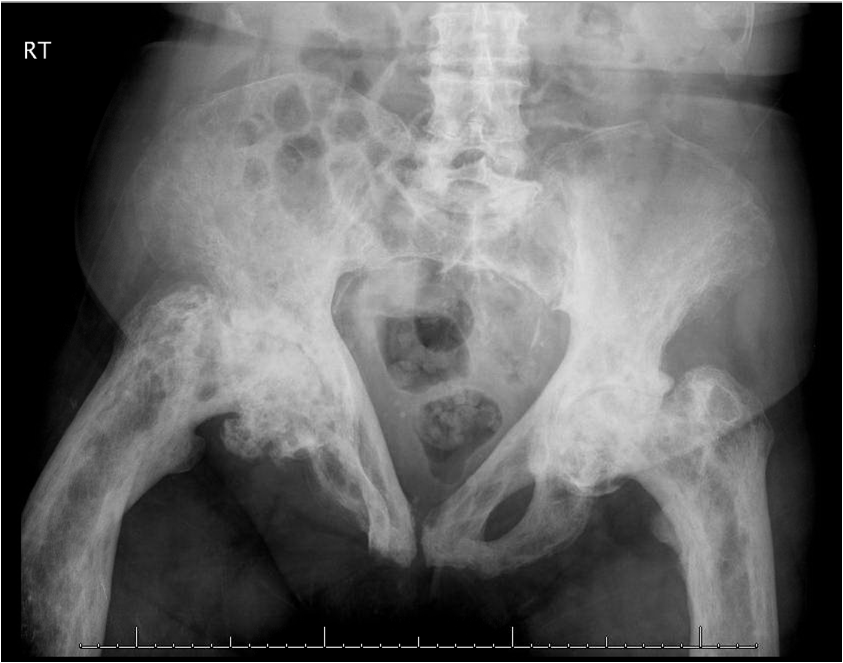

About 70% of patients with gout are treated exclusively in the primary care setting. Because the prevalence of gout is rising, particularly among older patients, you are increasingly likely to encounter this disease in your practice.

Gout is a primary care disease. About 70% of patients with gout are treated exclusively in the primary care setting. And because the prevalence of gout is increasing, particularly in older patients, you are increasingly likely to encounter this disease in your practice.